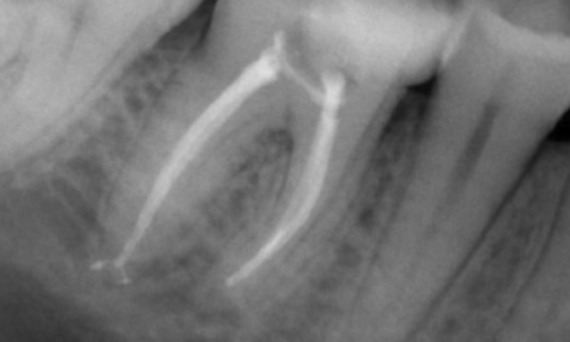

Un caso complesso con radici lunghe e sistema calcificato con un follow-up di 14 mesi

"Un successo incentrato sul paziente e sul processo." - Dott. Cowie

Prima: Radiolucenza periapicale associata principalmente alla radice distale e perdita della lamina dura sulla radice mesiale.

Dopo: TruNatomy è stata scelta in questo caso per consentire un approccio basato sulla carie e un’attenzione alla conservazione della dentina pericervicale, specialmente sull’aspetto mesiale in cui il dente aveva un restauro più minimo.